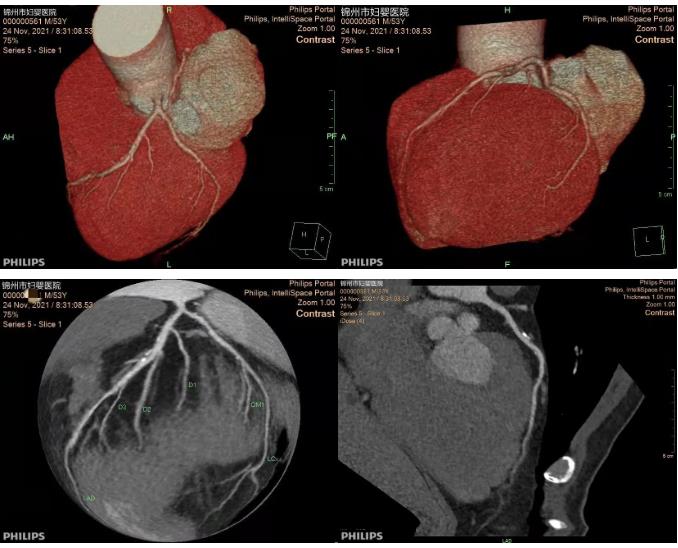

12-1020212021年11月24日,锦州市妇婴医院放射线科工作人员在放射线科主任曹焕带领下,由主治医师于福全、技师李一明相互合作,顺利完成院内首例冠状动脉CT血管成像检查,为临床科医生提供了准确的诊断...